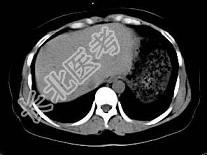

- 单项选择题根据所提供的图像,最可能的诊断是 ( )

A、正常肝血管

B、肝内胆管扩张

C、布-加综合征

D、肝血管瘤

E、以上都不是